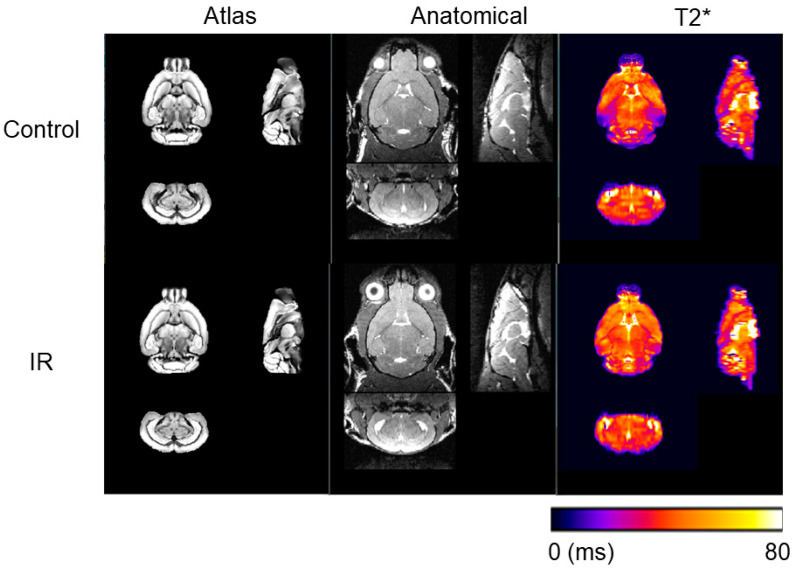

Background/Objectives: Radiation therapy can often lead to structural and functional changes in the brain resulting in radiation-induced brain injury. This study investigates the MRI-detectable effects of whole-brain irradiation across all neuroanatomical structures in adult mice, with a specific focus on T2* MRI measurements, to evaluate regions that may be particularly sensitive to iron accumulation. Methods: One year following irradiation or sham treatment, mice were imaged with a 7T MRI to evaluate changes in regional volume and T2* relaxation times across more than 652 neuroanatomical using the DSURQE mouse brain atlas. Results: Statistical analysis identified 301 altered regions with respect to regional volume and 85 regions with respect to T2* relaxation showing significant differences relative to the control group (p < 0.05). Further data refinement, including the consolidation of redundant, bi-lateral structures revealed 18 subregions with significant changes in both volume and T2*. The data refinement revealed that the most represented system was the olfactory system (8/18 regions, 44%). The olfactory regions also showed the most pronounced changes and greatest correlation between the two metrics. Conclusions: These findings are suggestive that ionizing radiation may cause a pronounced disruption in the olfactory system that coincides with potential iron accumulation.